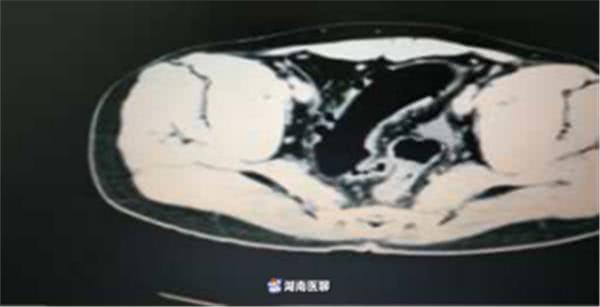

最近,衡陽(yáng)市中心醫(yī)院胃腸外科接診了一位患者——巨大腸道異物。腹部CT提示:橫結(jié)腸末端-降結(jié)腸-乙狀結(jié)腸長(zhǎng)條狀異常密度影,結(jié)合臨床病史,醫(yī)生考慮異物殘留可能。

(檢查結(jié)果)